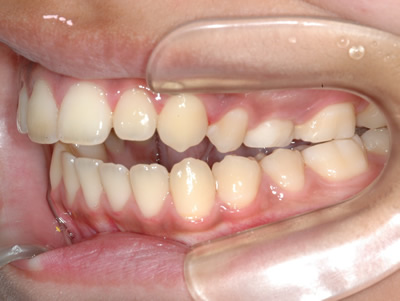

上顎の劣成長 (成長不足) による反対咬合で、上顎は拡大装置と上顎前方牽引装置を併用し前方方向への成長を促して前歯の咬み合わせを改善した後に、上下顎の前歯をマルチブラケット装置で並べました。治療の期間は2年でした。

初診時

1期治療終了時

2期治療終了時

| 費用の目安 | 440,000(税込) | |

| 治療期間の目安 | 2年 | |